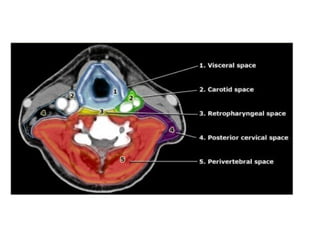

 De los 5 espacios profundos (espacios visceral,

carotídeo, cervical posterior, retrofaríngeo y

perivertebral), el visceral es el único específico del

cuello infrahioideo.

 El resto atraviesa tanto el cuello supra como

infrahioideo de forma vertical, por lo que los

procesos patológicos tienden a extenderse en esta

dirección.